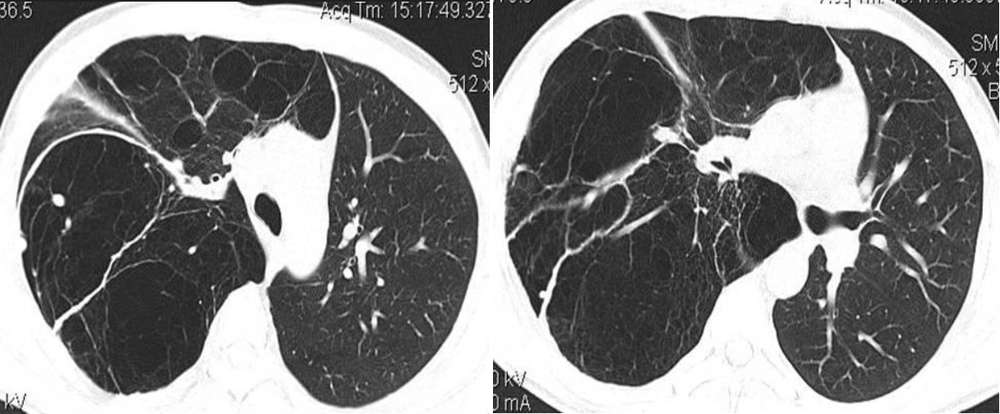

Thoracic CT scan confirmed that the whole of the right lung was replaced with cysts (image below). Therefore, a presumptive diagnosis of congenital cystic adenomatoid malformation (CCAM) was made, which was then confirmed by histologic examination.

Radiological abnormalities range from a soft-tissue mass containing single or multiple air-filled cysts of varying sizes to a solid homogeneous mass. CT imaging has a good accuracy in characterising the various types and is indispensable in identifying the true extent of the lesion [3].